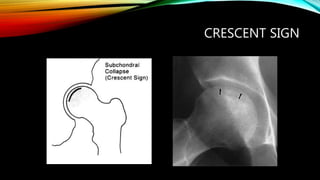

CRESCENT SIGN

HOW TO DIAGNOSE AVN OF

FEMORAL HEAD?

• Radiograph (X-ray or MRI)

-Ficet and Arlet classification system